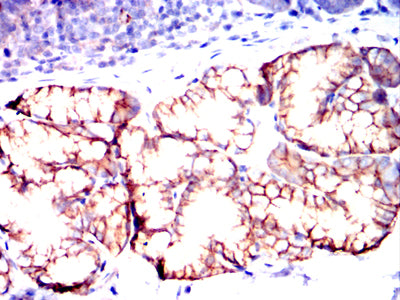

Immunohistochemical analysis of paraffin-embedded rabbit stomach tissues using CD82 mouse mAb with DAB staining.

Immunohistochemical analysis of paraffin-embedded rabbit small intestine tissues using CD82 mouse mAb with DAB staining.